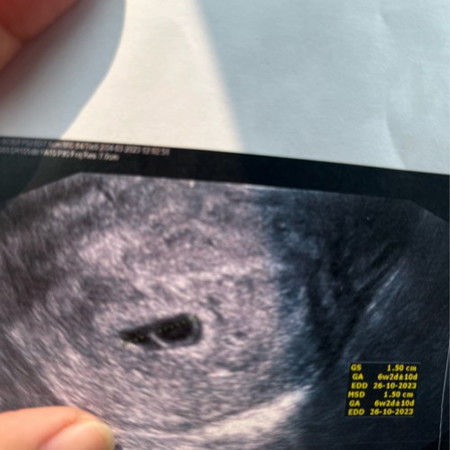

ตั้งครรภ์ประมาณ 6 สัปดาห์แบบนี้ ผิดปกติมั้ยคะ

คุณหมอแจ้งว่าอายุครรภ์ประมาณ 6 สัปดาห์ เจอแค่ถุงไข่แดงแบบนี้ ควรยุติการตั้งครรภ์มั้ยคะ